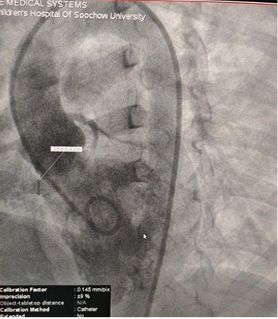

Case Sharing | Successful Closure of Multi-Exit Membranous Septal Aneurysm-Type VSD Using MemoSorb Biodegradable Occluder

Successful Closure of Multi-Exit Membranous Septal Aneurysm-Type VSD Using MemoSorb Fully Biodegradable Occluder

Base diameter: ~6.1 mm with multiple exit points

Membrane-like tissue observed over the defect

Color Doppler: Left-to-right shunt flow

Diagnosis: Perimembranous VSD

Challenge: Multiple exits + fragile membrane tissue

Selected MemoSorb ABFDQ-II 9 occluder based on intraoperative angiography and echocardiographic assessment.